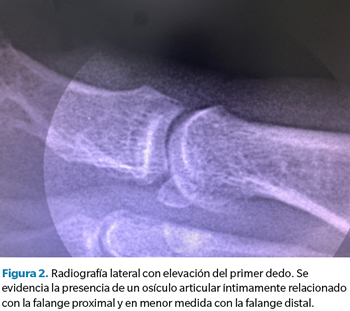

Ante la ineficacia del tratamiento conservador y las dificultades para la deambulación y el uso de calzado habitual que manifiesta la paciente, se realizan pruebas complementarias para valorar posibles soluciones quirúrgicas al problema, ya que la paciente desea una solución definitiva a su problema, descartando el uso de soportes plantares para efectuar una posible descarga en la zona. En primera instancia se realiza radiografía convencional lateral donde se evidencia la presencia de un osículo articular (Figura 2).